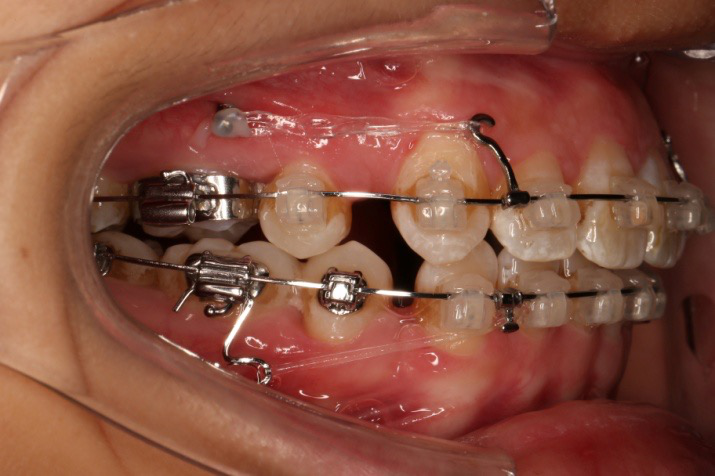

2018.03.01上TPA加17、27颚侧牵引钩,压低17、27颚尖下颌43、32重粘,下颌0.016*25niti

2018.04.20  间隙基本关闭,上颌重新整平,精调

2018.5.25  (19个月)拆TPA,16、26粘tube 上颌0.14*25cu-niti  下颌0.018*25niti2018.7.23  上颌 0.017*25TMA,下颌0.017*25ss43压低曲,双侧后牙垂直牵引

2018.09.29  15、43、16、17、11、21重粘,上0.016*25cu-niti 下0.018niti 上连扎